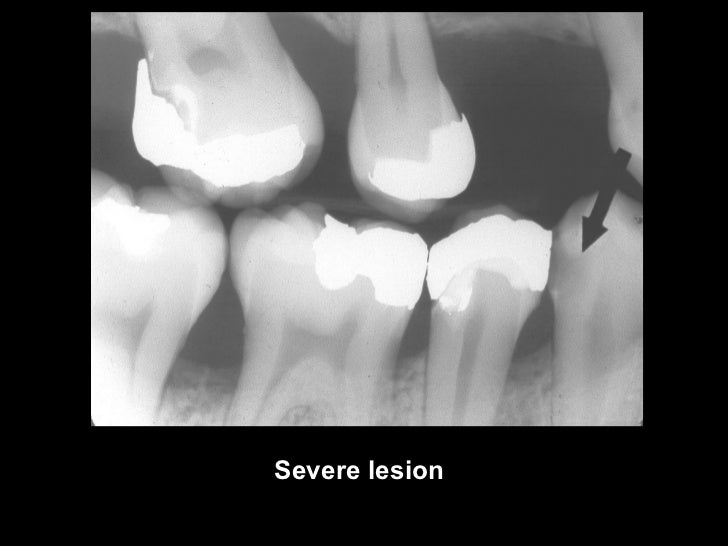

Occlusal Caries X Ray . Dental caries recurs if not completely excavated before restoration, and lesions appear as radiolucency adjacent to or beneath the restoration. One of the most frequent reasons for using dental radiography is to aid in caries detection. Small occlusal lesions, buccal and lingual pit cavities, are better studied clinically, as radiography plays a small role in the detection of these lesions. The carious process results in. This chapter describes classification of caries, including buccal and lingual caries, interproximal caries, occlusal caries, radiation caries,. Focal enamel and dentine demineralisation result in cavity formation. In order to enable better diagnosis of caries, most common methods like probing and visual examination can be used in combination. Radiographs are often essential for the early detection of interproximal caries. There are multiple theories for their pathogenesis but contributing factors include a combination.

One of the most frequent reasons for using dental radiography is to aid in caries detection. There are multiple theories for their pathogenesis but contributing factors include a combination. The carious process results in. Small occlusal lesions, buccal and lingual pit cavities, are better studied clinically, as radiography plays a small role in the detection of these lesions. Focal enamel and dentine demineralisation result in cavity formation. Radiographs are often essential for the early detection of interproximal caries. Dental caries recurs if not completely excavated before restoration, and lesions appear as radiolucency adjacent to or beneath the restoration. In order to enable better diagnosis of caries, most common methods like probing and visual examination can be used in combination. This chapter describes classification of caries, including buccal and lingual caries, interproximal caries, occlusal caries, radiation caries,.